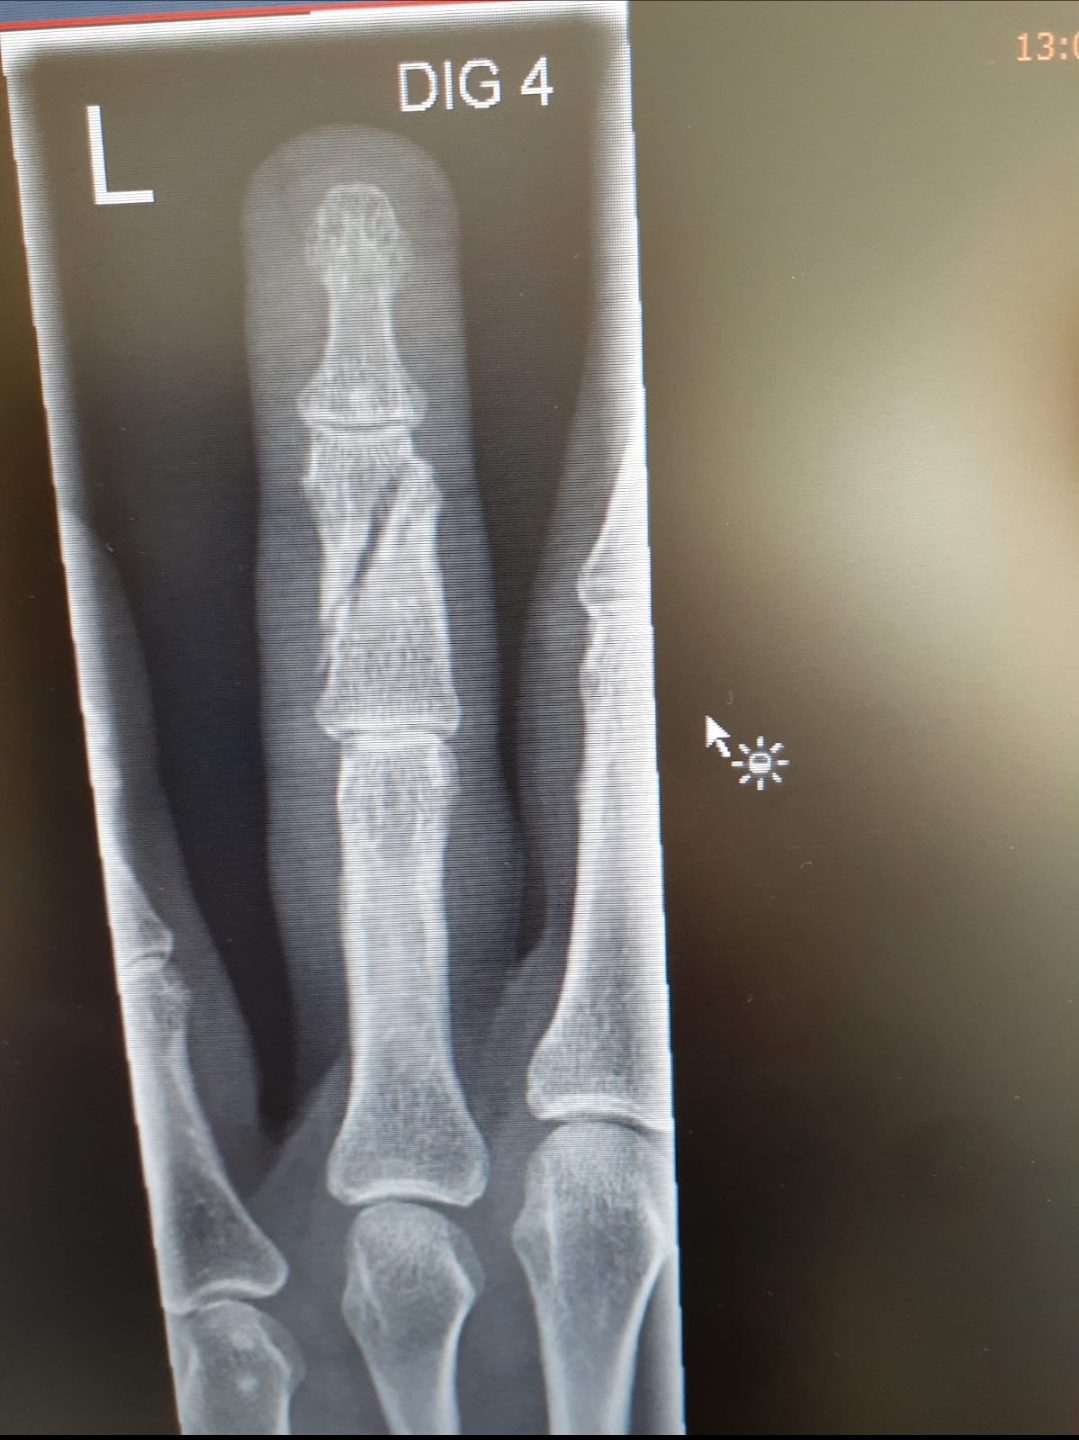

“Op dat moment brak mijn vinger.”

Er bestaan videobeelden van de terugkeer naar het bureau en van een deel van de aanhouding. Ook zijn er foto’s van de gebroken ringvinger. (zie onderaan deze pagina)

De rechter oordeelde uiteindelijk dat op basis van het beschikbare beeldmateriaal niet exact kon worden vastgesteld op welk moment de vingerbreuk ontstond. Daardoor kon het letsel niet strafrechtelijk worden toegerekend aan een individuele agent.

Volgens Stefan enkel omdat de rechter niet kon zien op beeld wanneer zijn vingen zou zijn gebroken tijdens de aanhouding.